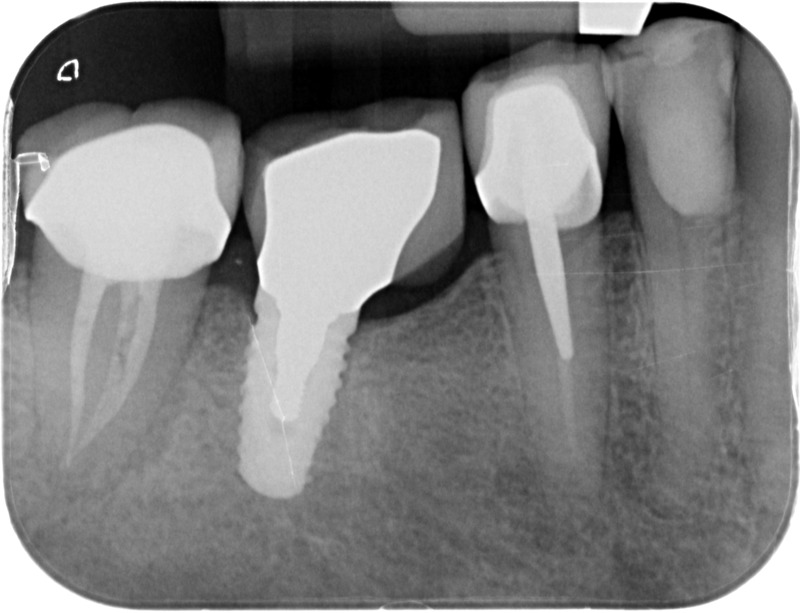

• Couronnes sur implants : Lorsqu’un implant est posé en remplacement des racines d’une dent, il est conçu pour recevoir d’abord un pilier vissé puis une couronne céramique. Le couple couronne - implant se substitue à la dent manquante pour en assurer les mêmes fonctions. Nous pouvons également adapter un bridge sur plusieurs implants dans le cas d’un édentement plus important.